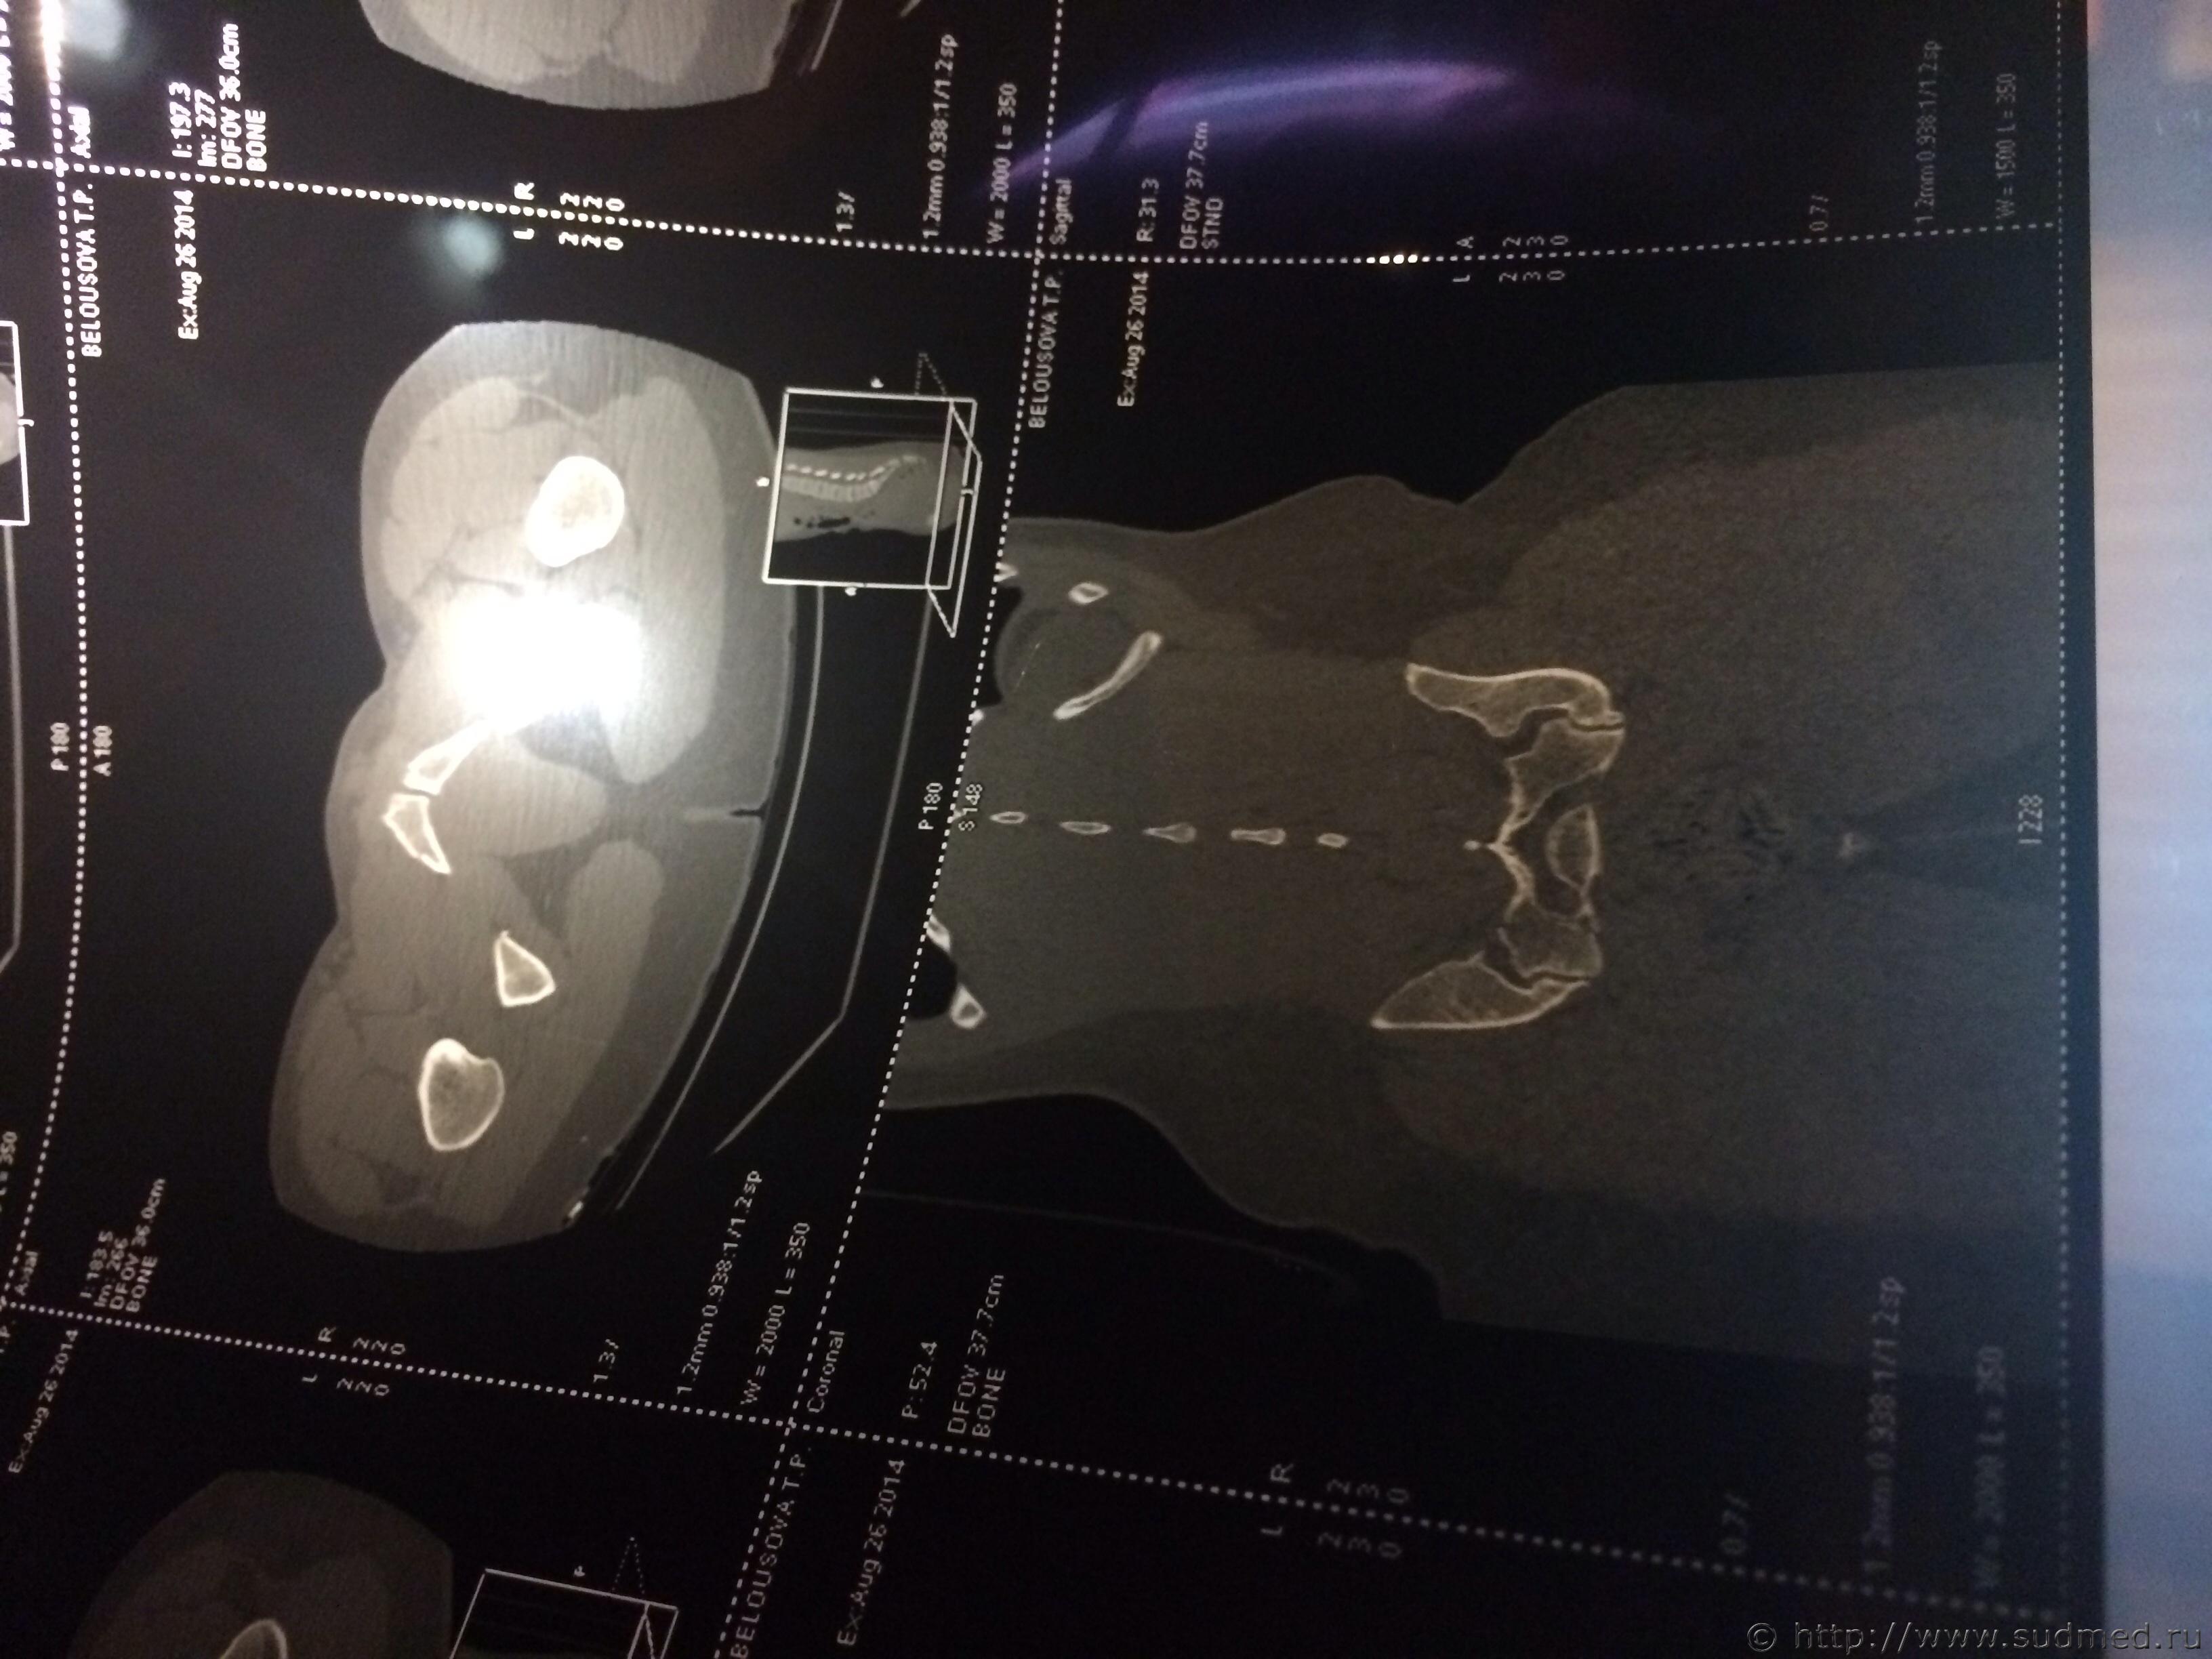

Спасибо! У меня результаты КТ, ошиблась)

КТ

Как мне видится - вертикальный перелом крестца. Тяжкий вред.

Впрочем, оставляю небольшую вероятность, что я не видел все сканы, да и качество их здесь, разумеется, хуже, чем изображение на пленке или на экране компьютера у врача, работающего на томографе.